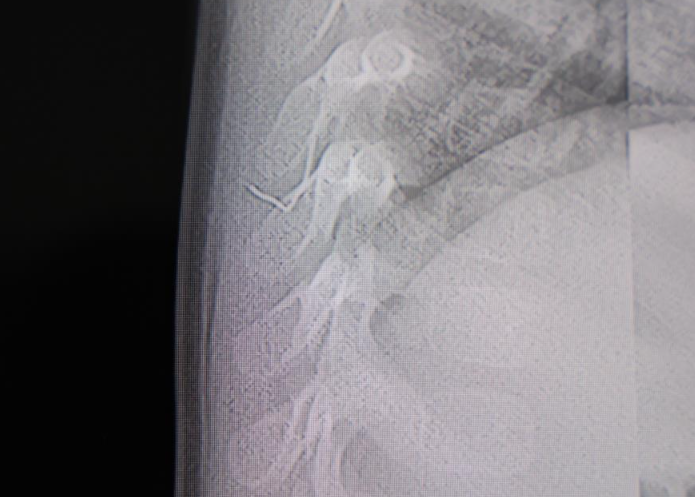

Aile, son olarak bebeğini HG Hospital’e getirdi. Beyin ve Sinir Cerrahisi Uzmanı Prof. Dr. İdris Altun tarafından yapılan tetkiklerde, yabancı cismin cilt altında, omurilik kanalına çok yakın bir bölgede bulunduğu ve akciğer zarına doğru ilerlediği tespit edildi.

Bebek, genel anestezi uygulanmadan; lokal anestezi ve sedasyon eşliğinde ameliyata alındı. Yapılan başarılı müdahalede yabancı cisim tamamen çıkarıldı. Cismin, ince zımba teline benzer metal bir tel olduğu ve yaklaşık 2 santimetre uzunluğunda bulunduğu belirlendi. Hasta, operasyonun ardından aynı gün taburcu edildi.

Operasyona ilişkin açıklama yapan Prof. Dr. İdris Altun, “Sırtında yabancı bir cisim olduğu söylenmiş ancak çıkarılamayacağı ve 8 yaşına kadar beklenmesi gerektiği ifade edilmişti. Bize başvurduğunda yaptığımız tetkiklerde, cilt altında, omurilik kanalına çok yakın ve akciğer zarına doğru ilerleyen bir yabancı cisim tespit ettik. Hastamızı tamamen uyutmadan, lokal anestezi ve sedasyon eşliğinde müdahale ederek lezyonu tamamen çıkardık” dedi.

Çıkarılan cismin yaklaşık 2 santimetre uzunluğunda metal bir tel olduğunu belirten Altun, “Bu yabancı cisim alınmasaydı enfeksiyon gelişebilir, omurilik kanalında ciddi hasarlar oluşabilirdi. Çocuk büyüdükçe cismin hareket etmesine bağlı olarak omurilikte zedelenmeler meydana gelebilirdi. Ayrıca yana doğru ilerleyerek akciğer zarına ve akciğere batma riski vardı. Bu durum enfeksiyona ve ilerleyen süreçte tümörle karışabilecek tablolara yol açabilirdi. Şu an hastamız gayet sağlıklı, gerekli kontrolleri yaptık ve aynı gün taburcu ettik” ifadelerini kullandı.